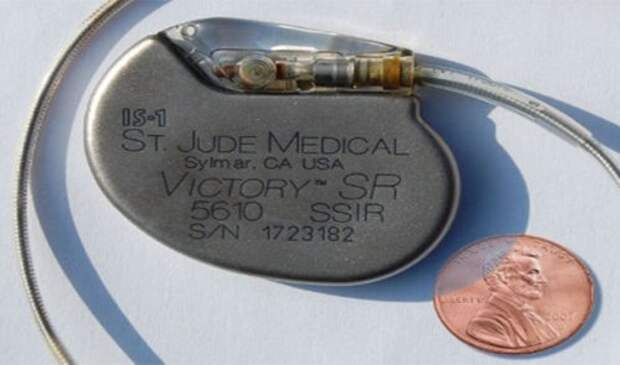

14. Кардиостимулятор (Pacemaker)

Конструируя осциллятор для записи звуков ударов сердца у животных в Корнельском университете (Cornell University), Уилсон Грэйтбатч (Wilson Greatbatch) случайно схватил неправильный транзистор. После включения устройства он обнаружил, что устройство издавало очень знакомый ритмичный пульсирующий звук, очень похожий на человеческое сердце.